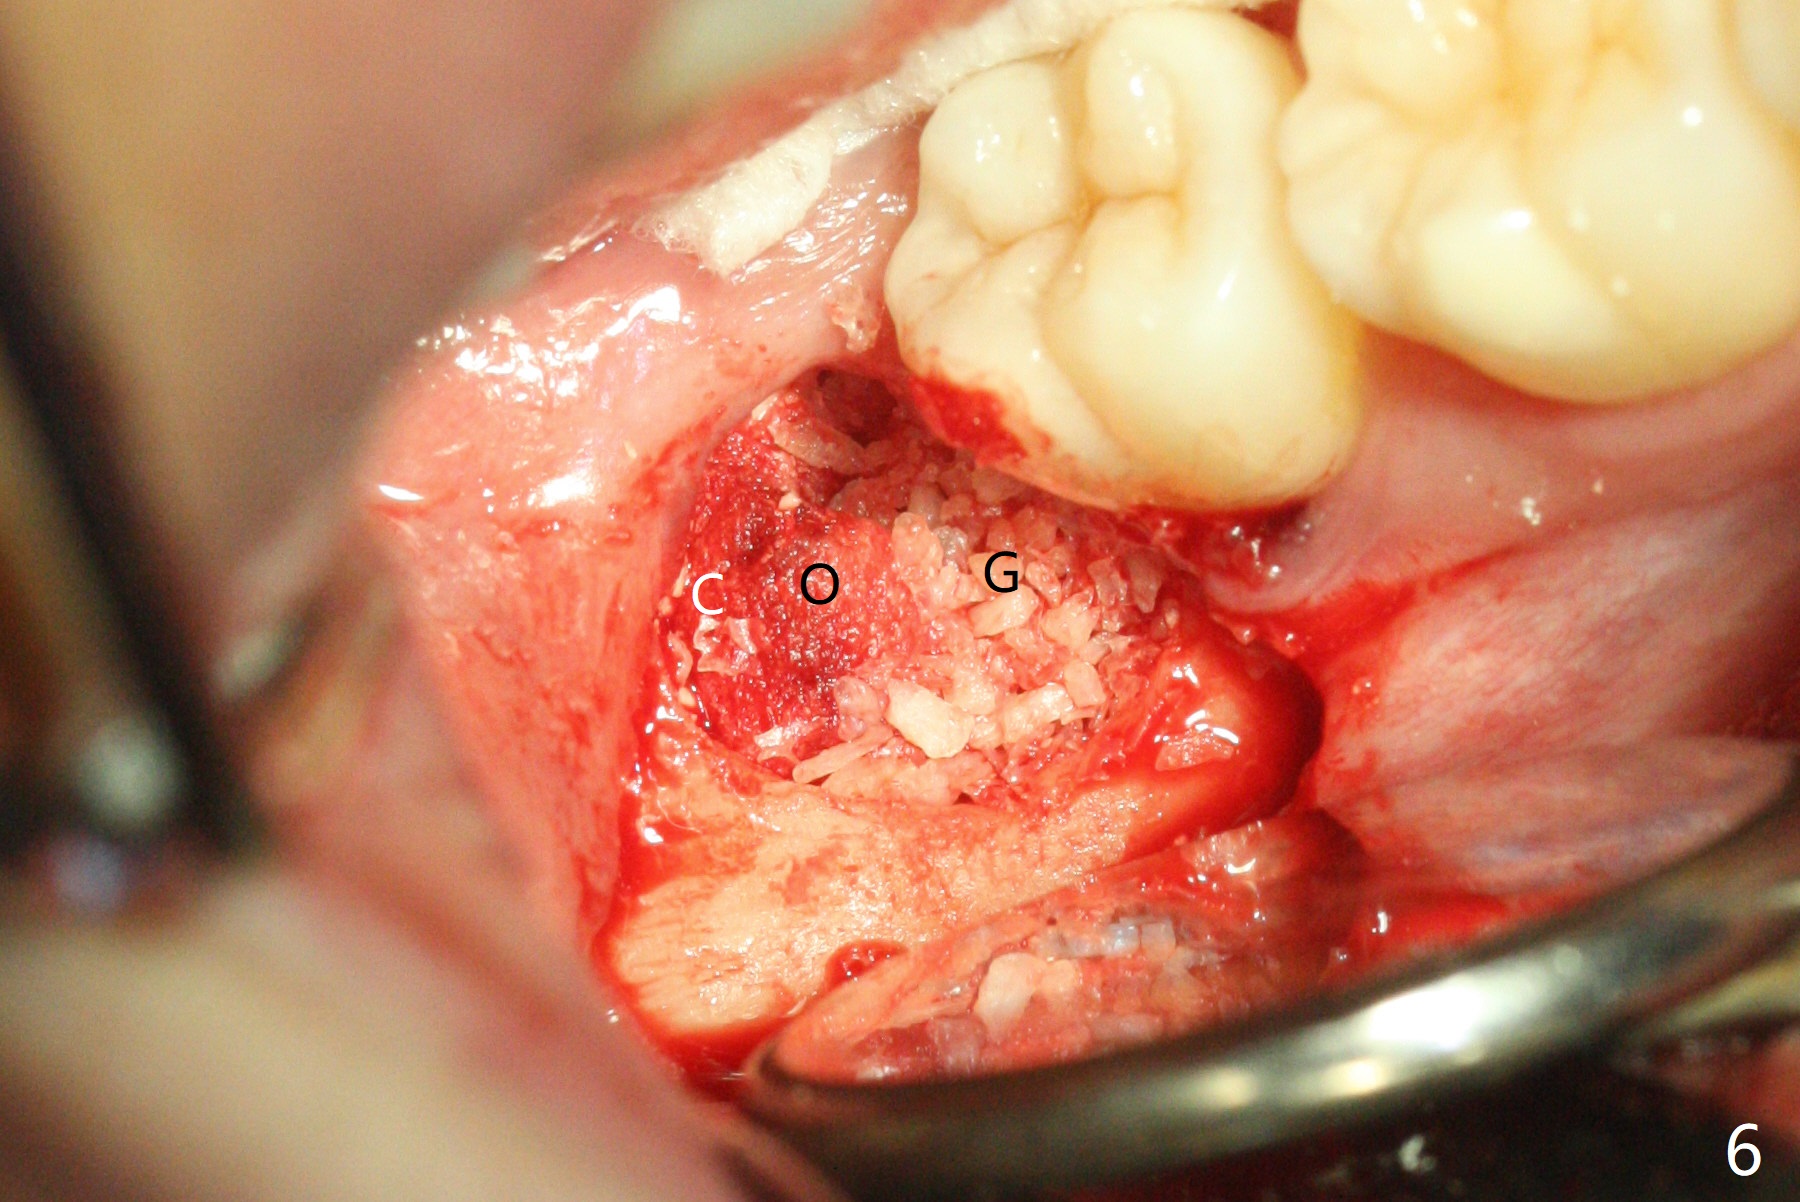

A 28-year-old woman returns for #17 and 32 extraction. To obtain full potential of bone regeneration after extraction, 3 D Bond (Graft Binder Cement, .5 cc, Fig.2 C) will be placed in the root portion of the socket of #32 , while allograft (G) and Collagen Plug (P) in the coronal one. For comparison, Osteogen Plug (Fig.3 O) will be inserted in the root portion of the socket of #17, while the other two materials same as those at #32. Take postop panoramic bitewing if both teeth are extracted. Otherwise take PA. Place the latter in the center of the extraction socket.

In fact the tooth #32 is extracted first; the defect involves the distobuccal aspect of the tooth #31 (Fig.4 *). An intraop PA is taken after extraction to confirm whether a broken surgical fissure bur tip retains or not; the distal lamina dura of #31 is low (Fig.5 *). It is expected to increase after cocktail bone graft (Fig.5' arrow). As planned, the bone cement (Fig.6 C) and allograft (G) are placed in the distal and mesial portions of the socket; between them is Osteogen Plug (O). Another piece of Osteogen Plug (as collagen membrane for bone graft) is placed on the top of the socket before suturing with 4-0 Plain Gut (Fig.7,7' O). Also note the bone graft being placed distobuccal (CT study) to #31 (Fig.7' red dashed line) to reduce possibility of future periodontitis. The patient returns 15 days postop with chief complaint of mild pain since extraction, although the wound looks normal. The transverse cortex connecting to the lamina dura (Fig.5 *) is obliterated when allograft is placed (Fig.7 G). The part of the graft remains in place 1 month postop (Fig.9) in spite of wound dehiscence (Fig.8). The bone graft loss is indicated by the fact of the reappearance of the transverse cortex (Fig.9). In the same appointment, the tooth #17 (Fig.10) is being extracted (Fig.11), leaving a defect mesiobuccal (Fig.12 *) to distal (curette). Part of Osteogen plug (Fig.13 O) is stretched to cover the mesially placed allograft (Fig.14 G). One quarter of Collagen plug is placed over the Osteogen plug (Fig.13 O) before 4-0 PGA suturing. There is bone regeneration 1 year postop (Fig.15,16).